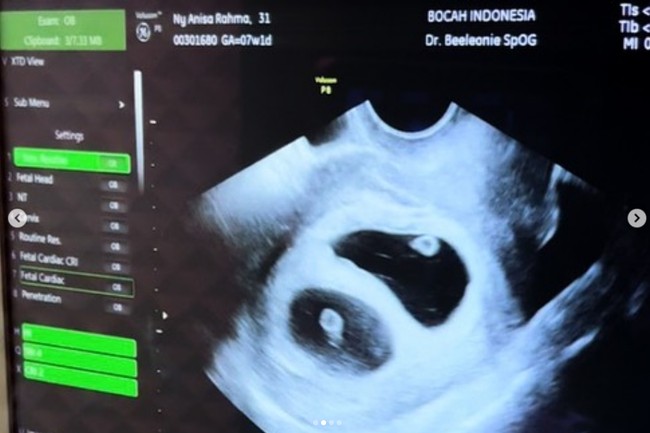

Potret Anisa Eks Cherrybelle Hamil Anak Kembar, 4 Tahun Penantian Garis Dua

Jakarta - Anisa eks Cherrybelle memberikan kabar bahagia. Setelah empat tahun penantian, Anisa dinyatakan hamil anak kembar. Seperti apa potret kebahagiannya?